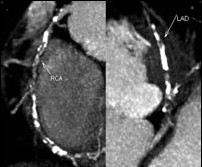

随着CT扫描技术的飞速发展,CT时间分辨率和空间分辨率已有了显著提高,CT-CA可以清晰地显示冠状动脉的解剖学结构,并评价直径为1.5 mm的冠状动脉内狭窄情况。CT-CA图像的可诊断率为100%,诊断冠状动脉狭窄的敏感性、特异性、阳性预测值和阴性预测值分别为94%、97%、87%和99%。与CA相比,CT-CA不仅可以判断管腔的狭窄程度,还可显示冠状动脉壁和粥样硬化斑块,这是CA所不能比拟的。

图1 CT-CA示3支病变,左前降支(LAD)、右冠状动脉(RCA)中远段闭塞